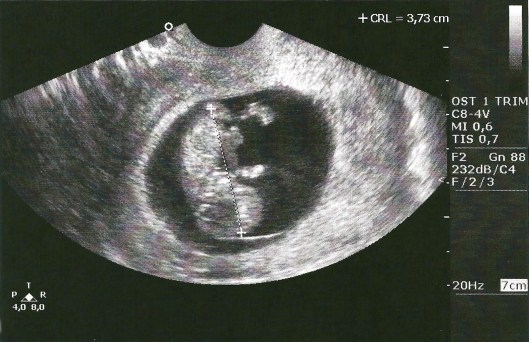

And now I proudly present to you, the first pictures of our baby!

We are praising God tonight for a healthy baby and pregnancy thus far and looking with new expectation toward his or her expected arrival on (or around) January 31st!